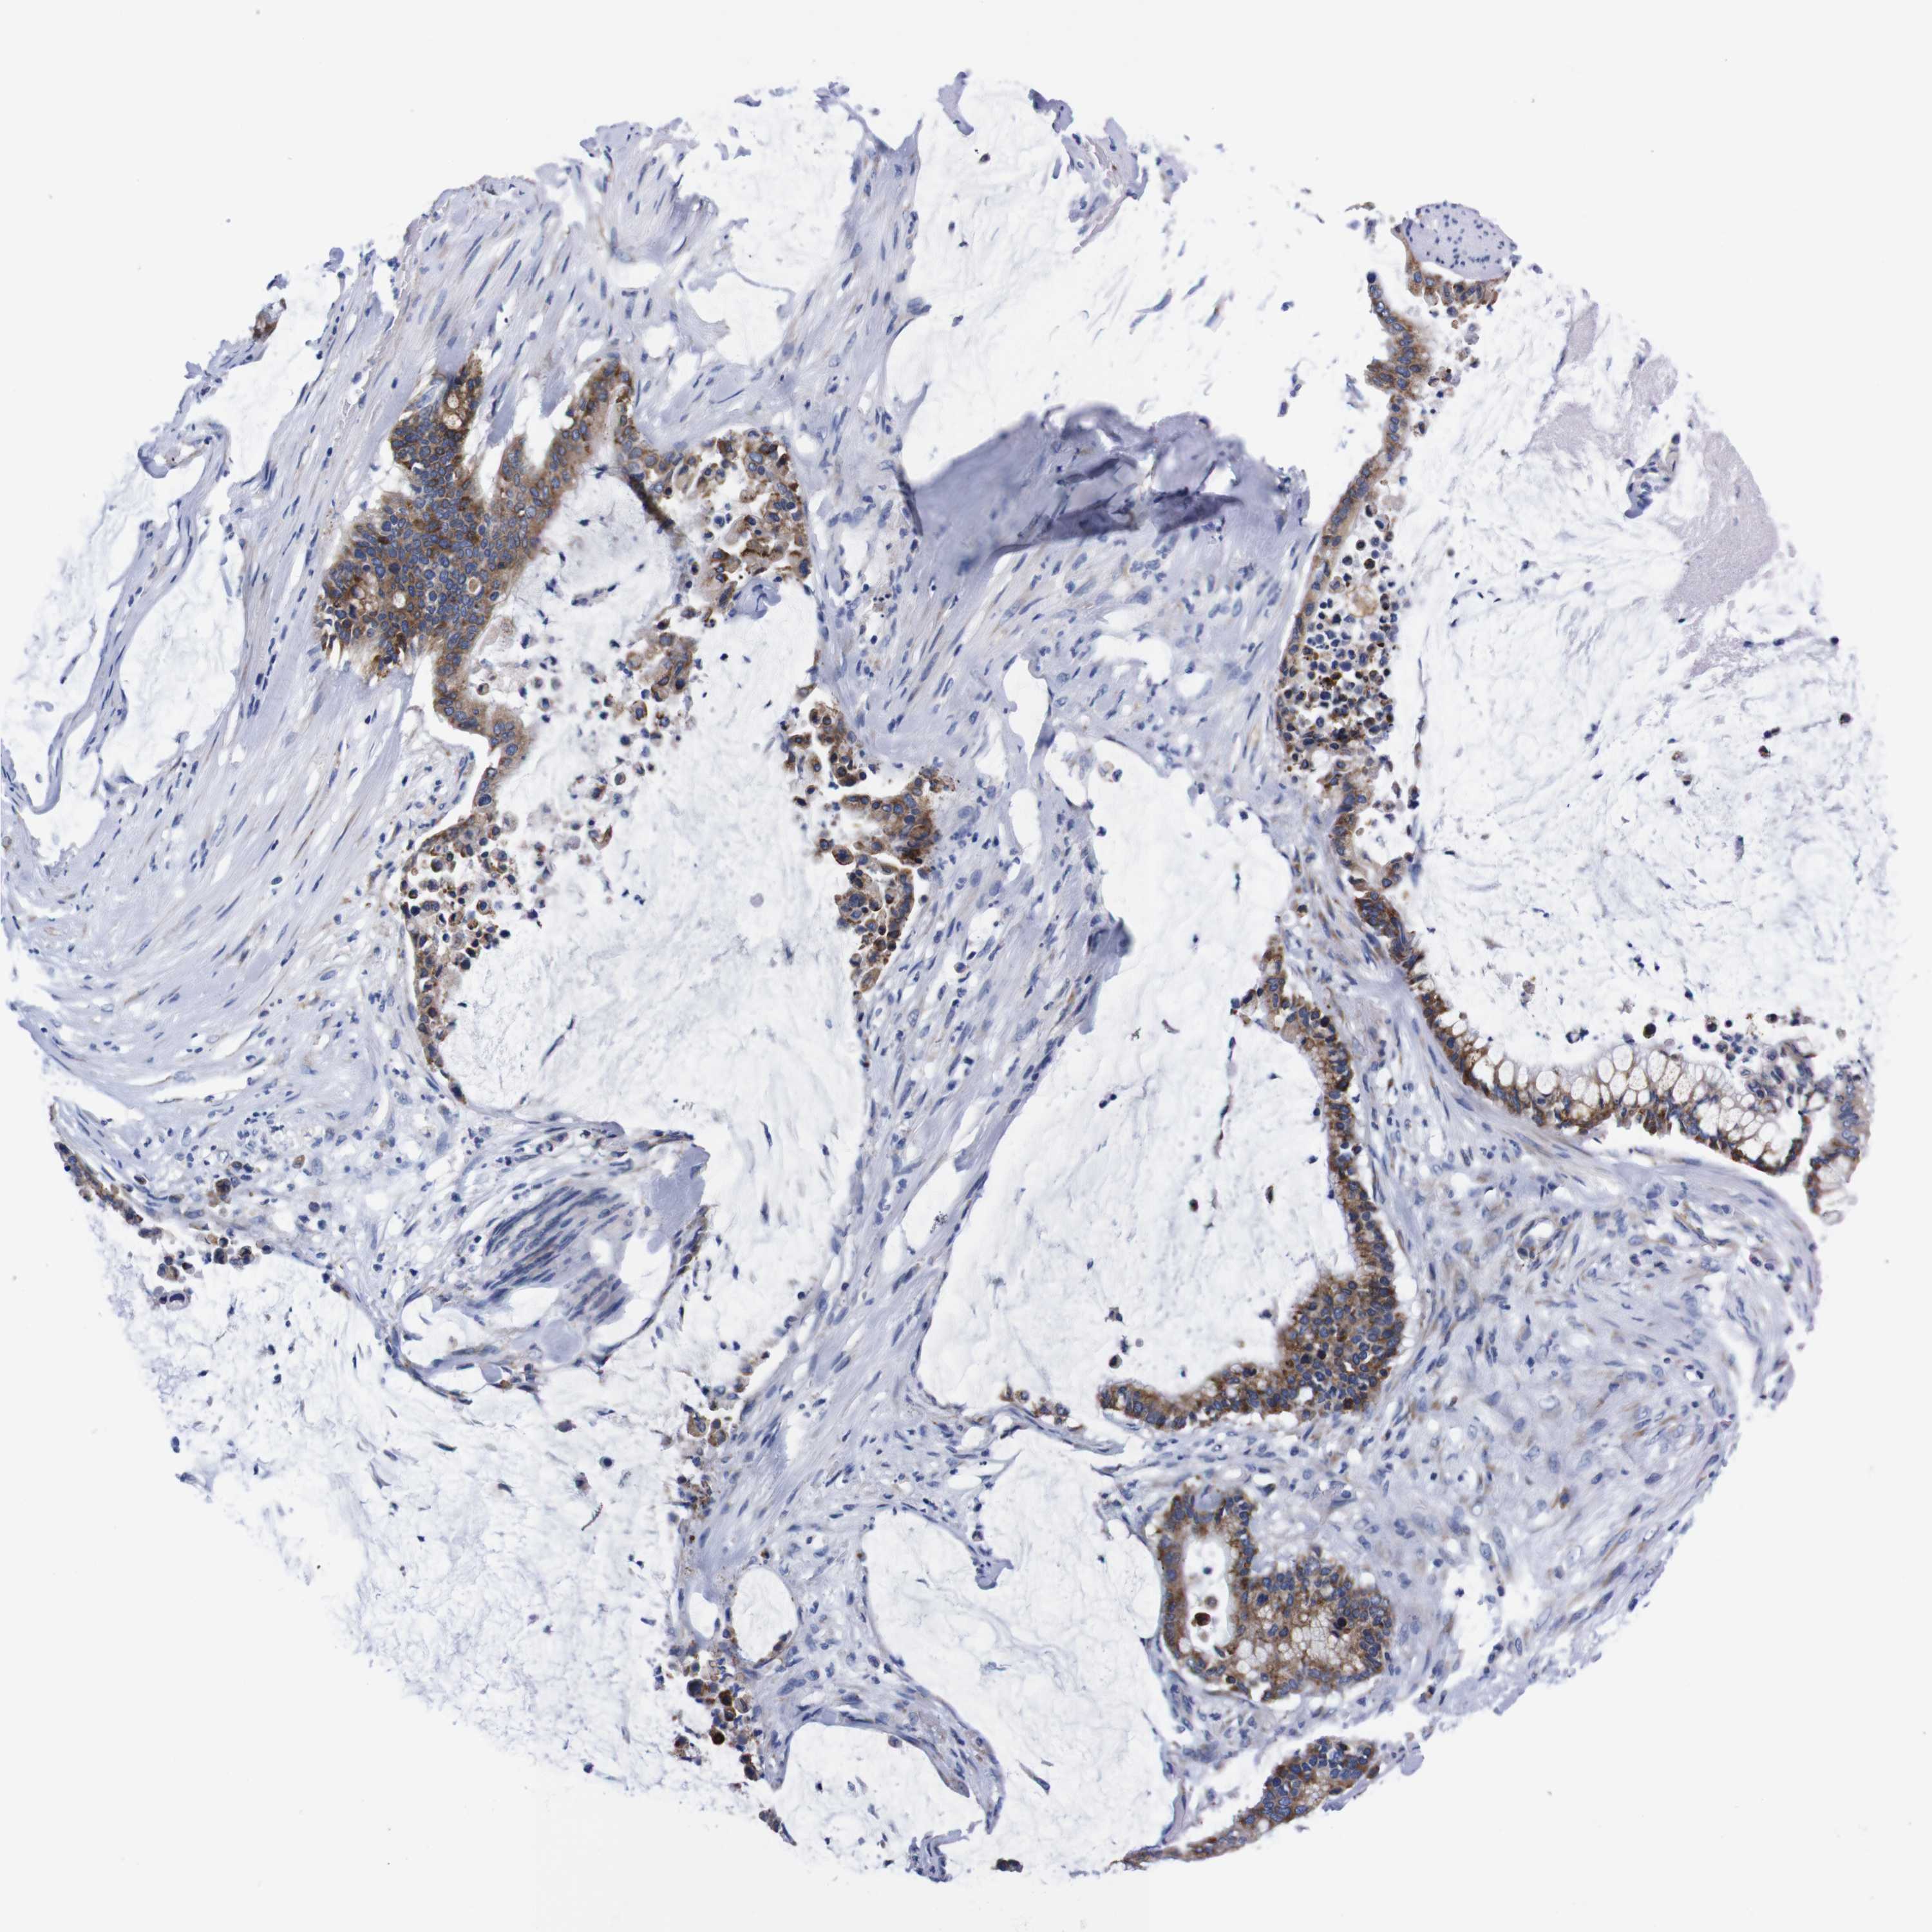

PANCREATIC CANCER - Protein expressioni

A mouse-over function shows sample information and annotation data. Click on an image to view it in a full screen mode. Samples can be filtered based on level of antibody staining by selecting one or several of the following categories: high, medium, low and not detected. The assay and annotation is described here.

Note that samples used for immunohistochemistry by the Human Protein Atlas do not correspond to samples in the TCGA dataset.

Antibody stainingi

Antibody staining in the annotated cell types in the current human tissue is reported as not detected, low, medium, or high, based on conventional immunohistochemistry profiling in selected tissues. This score is based on the combination of the staining intensity and fraction of stained cells.

Each image is clickable and will lead to virtual microscopy that enables deeper exploration of all samples and also displays staining intensity scores, fraction scores and subcellular localization as well as patient and tissue information for each sample.

Antibody HPA013994

Antibody HPA013995

Adenocarcinoma, NOS